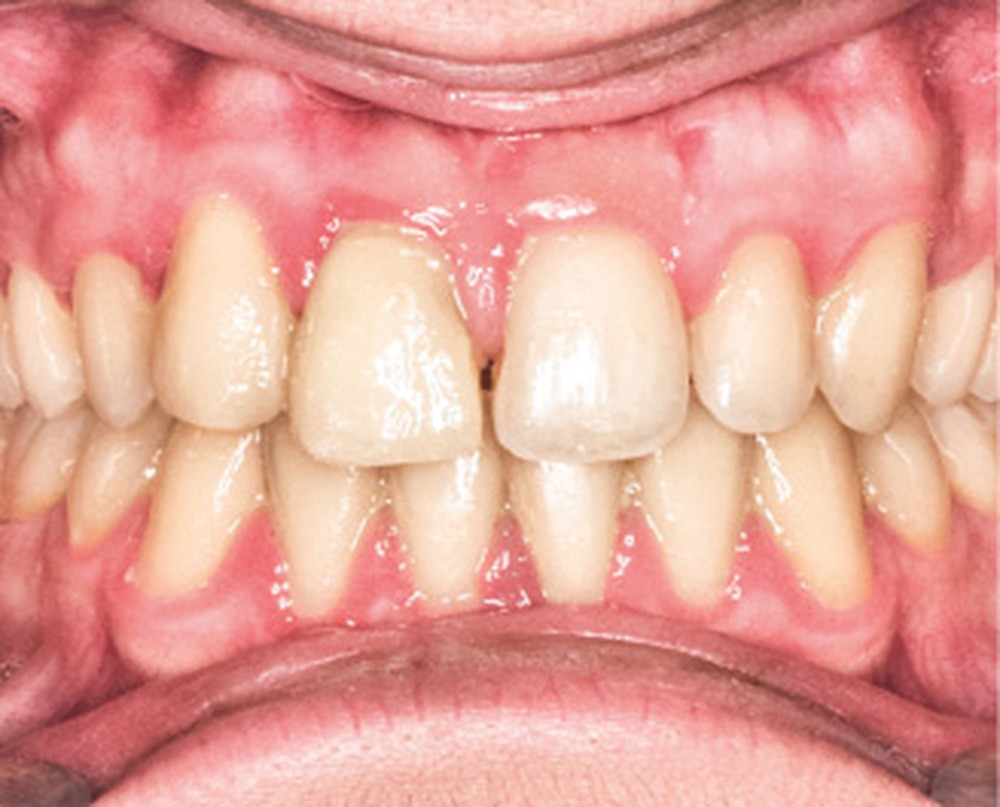

D’un point de vue occlusal, le patient, en denture adulte jeune stable, présente une classe II d’Angle bilatérale de 4 mm, associée à un encombrement maxillaire de 5 mm et mandibulaire de 2 mm. La face mésiale de 21 est centrée avec le plan sagittal médian, la non-concordance des médianes incisives est d’origine mandibulaire (déviation de la médiane mandibulaire vers la gauche) (fig. 1b-d).

Son incisive centrale supérieure droite (11) présente un défaut de structure amélaire sévère, compromettant une technique restaurative pérenne a minima. L’examen de la panoramique (fig. 1e) et de la radiographie rétroalvéolaire de 11 (fig. 1f) objective une fracture coronaire verticale, ainsi qu’une racine grêle et courbe, peut-être en rapport avec un ancien traumatisme [1]. Le rapport couronne clinique/racine clinique est défavorable.